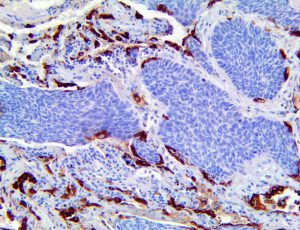

The first cytokines released are interleukin 1β (IL-1β) and tumor necrosis factor-α (TNF-α), which attract a variety of circulating white blood cells (WBCs) to the infection site, including neutrophils, monocytes, macrophages, and natural killer (NK) cells. This response, along with the antipathogenic chemicals released by these cells (i.e., complement), comprise the innate immune response. These cells directly attack the invading pathogen and also release additional cytokines, chief among them interleukin-1 and 6 (IL-6). IL-6 is essential for invoking the adaptive immune response, which calls T-cells, B-cells, and T helper (Th) cells to the infection site. IL-6 also stimulates further recruitment, proliferation and activation of macrophages.

This activation induces inflammatory monocytes to highly express IL-6, starting a localized and then systemic cascade effect that results in hyperproduction of IL-6, which accelerates the inflammatory process. Because IL-6 also increases vascular permeability, excessive levels cause blood vessels to become very leaky. This, along with clotting factors released from vascular endothelial cells, stimulates the coagulation cascade, resulting in microthrombosis (tiny clots), which leads to ischemia and tissue death of the kidney, intestines, heart, liver, brain and extremities.